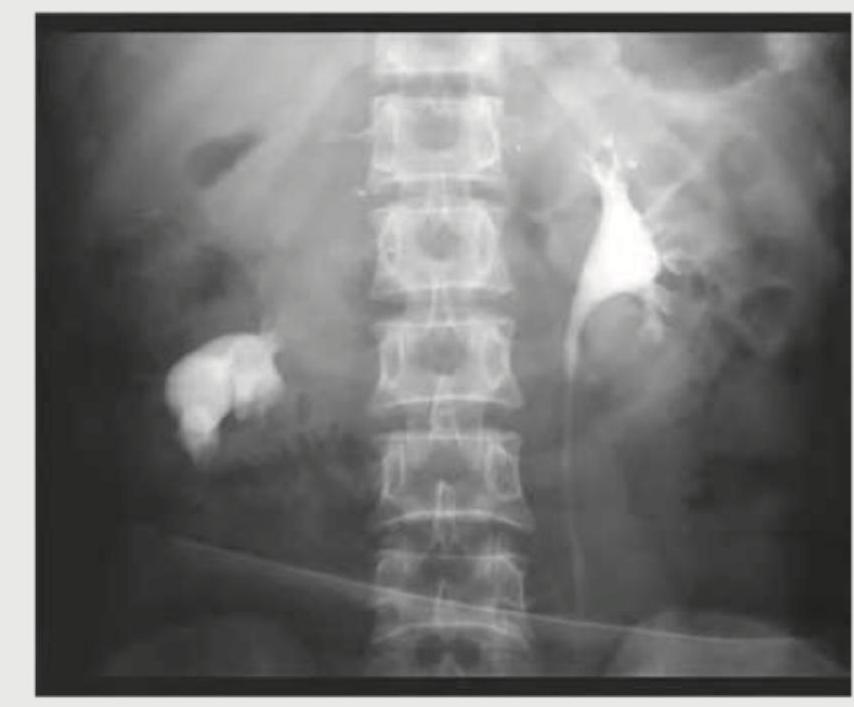

Excretory urogram in a two-year-old child with recurrent UTI shows:

Question 13: Excretory urogram in a two-year-old child with recurrent UTI shows:

- A. Drooping water lily sign (Correct Answer)

Explanation: ***Drooping water lily sign*** - This sign is characteristic of a **duplex collecting system** with a **dilated, obstructed upper pole ureter** and calyx, typically associated with an **ectopic ureterocele**. - The displaced lower pole calyces are pushed laterally and inferiorly by the dilated upper pole system, creating the appearance of a "drooping lily" or "drooping flower." - In children with recurrent UTIs, this finding indicates an underlying anatomical anomaly—specifically an **obstructed upper pole moiety in a duplex kidney**—which predisposes to stasis and infection. - **Most specific sign** for this condition on excretory urogram. *Horse shoe kidney* - A **horseshoe kidney** is a congenital fusion anomaly where the two kidneys are fused (usually at lower poles) across the midline. - Characteristic IVU findings include medially oriented lower poles, high ureteric insertion, and abnormal renal axis. - Does not cause the drooping lily appearance or typically present with recurrent UTI in this pattern. *Flower vase kidney* - **Flower vase sign** is a recognized radiological finding describing the appearance of **infundibular stenosis**, where the calyx is dilated but the infundibulum (connecting neck) is narrowed, resembling a flower vase. - This is a different entity from the drooping lily sign and represents focal obstruction at the infundibulum level rather than upper pole obstruction in a duplex system. - Not associated with the clinical scenario of recurrent UTI in a child with duplex kidney anomaly. *Duplication of kidney* - While a **duplex collecting system** (duplicated collecting system) is indeed present in this condition, this is a descriptive anatomical term rather than a specific radiological sign. - The **drooping water lily sign** is the more precise and specific descriptor for the characteristic IVU appearance of an obstructed upper pole moiety in a duplex kidney. - "Duplication" alone does not convey the specific pathology (obstruction) causing the recurrent UTIs.

Question 14: What is the radiological sign that could best describe this image?

- A. Cobra head sign (Correct Answer)

Explanation: ***Cobra head sign*** - This sign is seen in the setting of a **ureterocele**, which is a cystic dilatation of the intravesical (within the bladder) portion of the ureter. - On intravenous urography (IVU) or retrograde pyelography, the dilated ureterocele appears as a filling defect within the bladder, outlined by contrast, creating the characteristic "cobra head" or "spring onion" appearance. *Rim sign* - The **rim sign** is typically associated with **renal calculi** (kidney stones). - It refers to a thin rim of soft tissue or gas surrounding a radiolucent stone, which can sometimes be seen on CT scans. *Fish hook bladder* - This term describes the shape of the bladder in cases of **benign prostatic hyperplasia (BPH)**. - Due to the enlarged prostate elevating and distorting the bladder base, the contrast-filled bladder appears elongated and curved, resembling a fish hook on a cystogram. *Soap bubble* - The "soap bubble" appearance is often used to describe **multiloculated cystic masses** or certain types of tumors, particularly in bone lesions (e.g., aneurysmal bone cyst, fibrous dysplasia). - It refers to multiple small, rounded lucencies giving a bubbly or multicystic appearance on imaging.